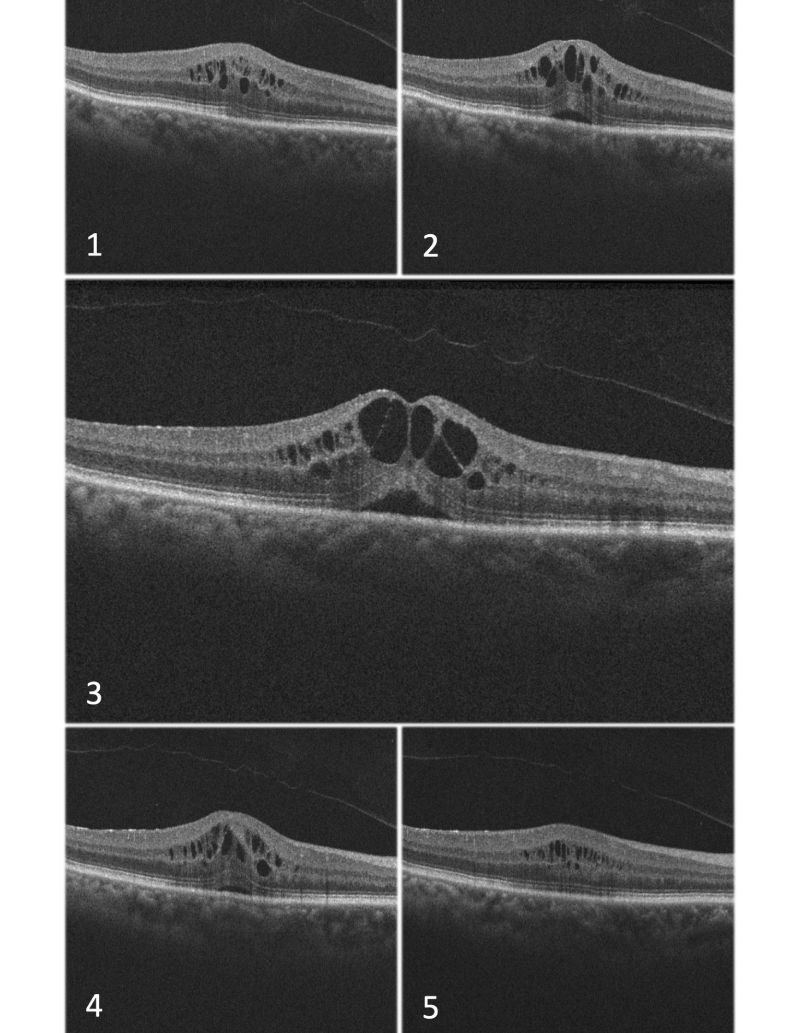

cme with optically empty areas

Cystoid Macular Edema (CME) with optically empty areas (OEA), different sections of Optical Coherence Tomography (OCT) images

Harnessing the imaging power of OCT, Dr. Tezel and his study team theorized that characterizing tissue changes due to fluid accumulation in the retina as they occur through time could provide much-needed insights into the disease progression of macular edema. “Light reflection within the retina will diminish as it travels through pockets of fluid, and these areas will show as black on the OTC scan, or an optically empty area (OEA),” explains Dr. Tezel. “Thus, comparing the total black area within an OCT scan can give us an idea about the relative hydration of the sensory retina.”